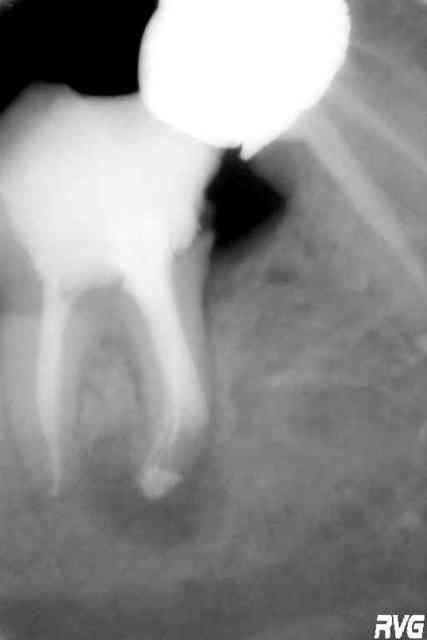

je ne comprends pas l'acharnement sur cette dent, mon sbire, abstraction faite de la qualité de ton travail.

Audi tt 2007 jzsdts - Eugenol

j'avais un peu de temps...et puis ma formation implanto est pas finie, faut faire durer...:)

Pa050055 igyagy - Eugenol

... et la beauté du geste!